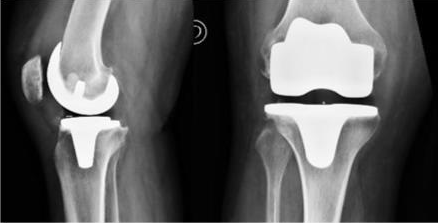

There are currently three types of knee prostheses that allow replacement and resurfacing of the articular surfaces of worn or destroyed compartments:

- Total prosthesis that concerns the three compartments of the knee: internal femoro-tibial, external and femoro-patellar.

Total knee replacement

Total knee replacement is indicated when physiotherapy, conservative medical, and surgical treatments are ineffective.

This procedure eliminates pain associated with wear and tear, restores satisfactory knee mobility, and a comfortable quality of life. The results are generally very satisfactory in patients 70 years of age or older. For younger patients with more active lives (who require implants for longer and more intensively), conservative surgical interventions such as osteotomy are preferred.